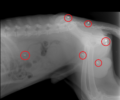

Την επόμενη μέρα ο Πάκο μεταφέρθηκε σε κτηνίατρο στην Κω και οι ακτινογραφίες έδειξαν πως είχε πυροβοληθεί από κοντά στο κεφάλι. Το κρανίο, όπως μπορείτε και εσείς να διαπιστώσετε, είναι γεμάτο σκάγια. Το δεξί του μάτι είναι κατεστραμμένο εντελώς και το αριστερό έχει ελάχιστες πιθανότητες να επανέλθει μερικώς. Ο Γιώργος Νούσιος και η Αγγελική Ζησιμοπούλου κάνουν έκκληση σ’ εκείνους που γνωρίζουν να καταγγείλουν τον δράστη ώστε ο ένοχος να δικαστεί.